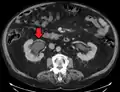

Left sided hydronephrosis in a person with an atrophic right kidney. Stent is also present (image below).

Left sided hydronephrosis, coronal view. Stent is also present.

Treatment of hydronephrosis focuses upon the removal of the obstruction and drainage of the urine that has accumulated behind the obstruction. Therefore, the specific treatment depends upon where the obstruction lies.[12]

Acute obstruction of the upper urinary tract is usually treated by the insertion of a nephrostomy tube. Chronic upper urinary tract obstruction is treated by the insertion of a ureteric stent or a pyeloplasty.[11]

Lower urinary tract obstruction (such as that caused by bladder outflow obstruction secondary to prostatic hypertrophy) is usually treated by insertion of a urinary catheter or a suprapubic catheter. Surgery is not required in all prenatally detected cases.[19]